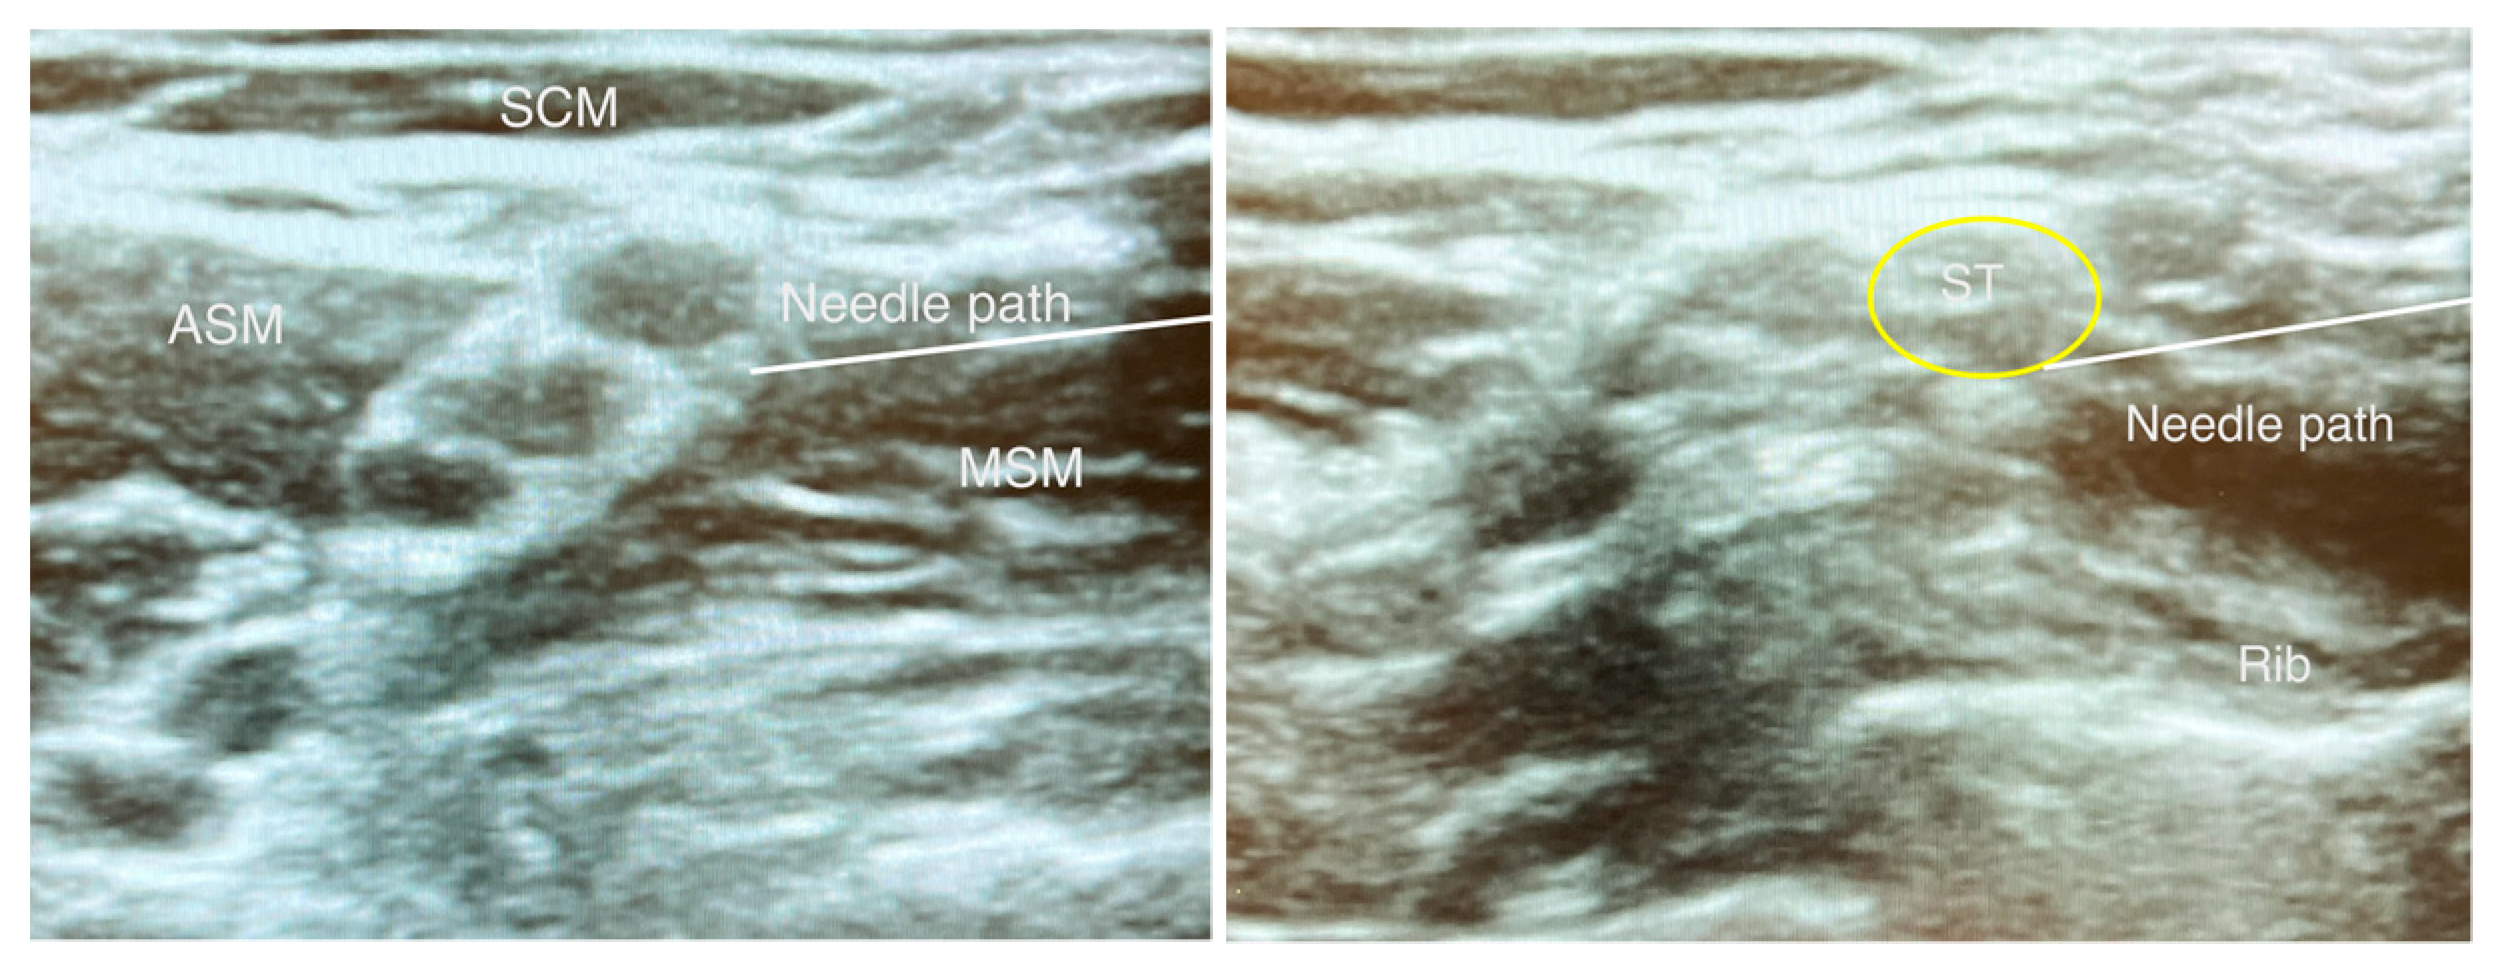

3.1. Superior Trunk Block